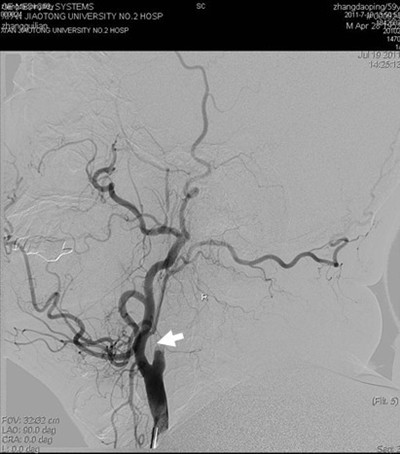

(图1) 造影见左侧颈内动脉开口附近闭塞(箭头所示),颅内血管未显影

患者张某,59岁,以左侧肢体活动不灵14天入院,14天前患者突然出现左侧肢体无力,活动受限,并言语含糊,曾于外院就诊,脑CT及MR提示脑梗死,治疗后效果不明显,遂来我院。既往有高血压史数年,长期间断服降压药。入院查体:血压180/100mmHg,左侧口角低,左侧鼻唇沟浅,左侧上下肢瘫痪,肌力III+,左侧肢体共济运动差,左侧巴氏征阳性。余查体未见明显异常。辅助检查:空腹血糖9.8mmol/l。根据患者病史、外院影像学检查,考虑诊断为1.脑梗死(分水岭区);2.高血压病(III级,极高危);3.糖尿病(2型)。为了进一步明确患者脑梗死病因,确定下一步治疗方案,在家属签字同意下,于2011年7月19日进行了全脑血管造影术,术中发现右侧颈内动脉开口处闭塞,但远端血流通过后交通依稀可见,经过我科介入小组缜密讨论,拟给患者行闭塞血管再通手术,经过2小时的紧张手术,取得了很好的手术效果,患者安返病房(见图)。本次手术的成功,是继6月我们对急性闭塞血管进行取栓,我院神经介入工作的又一次突破,在血管闭塞后14天再通,在国内外少见报道,这将快速推动神经介入工作的进一步发展。